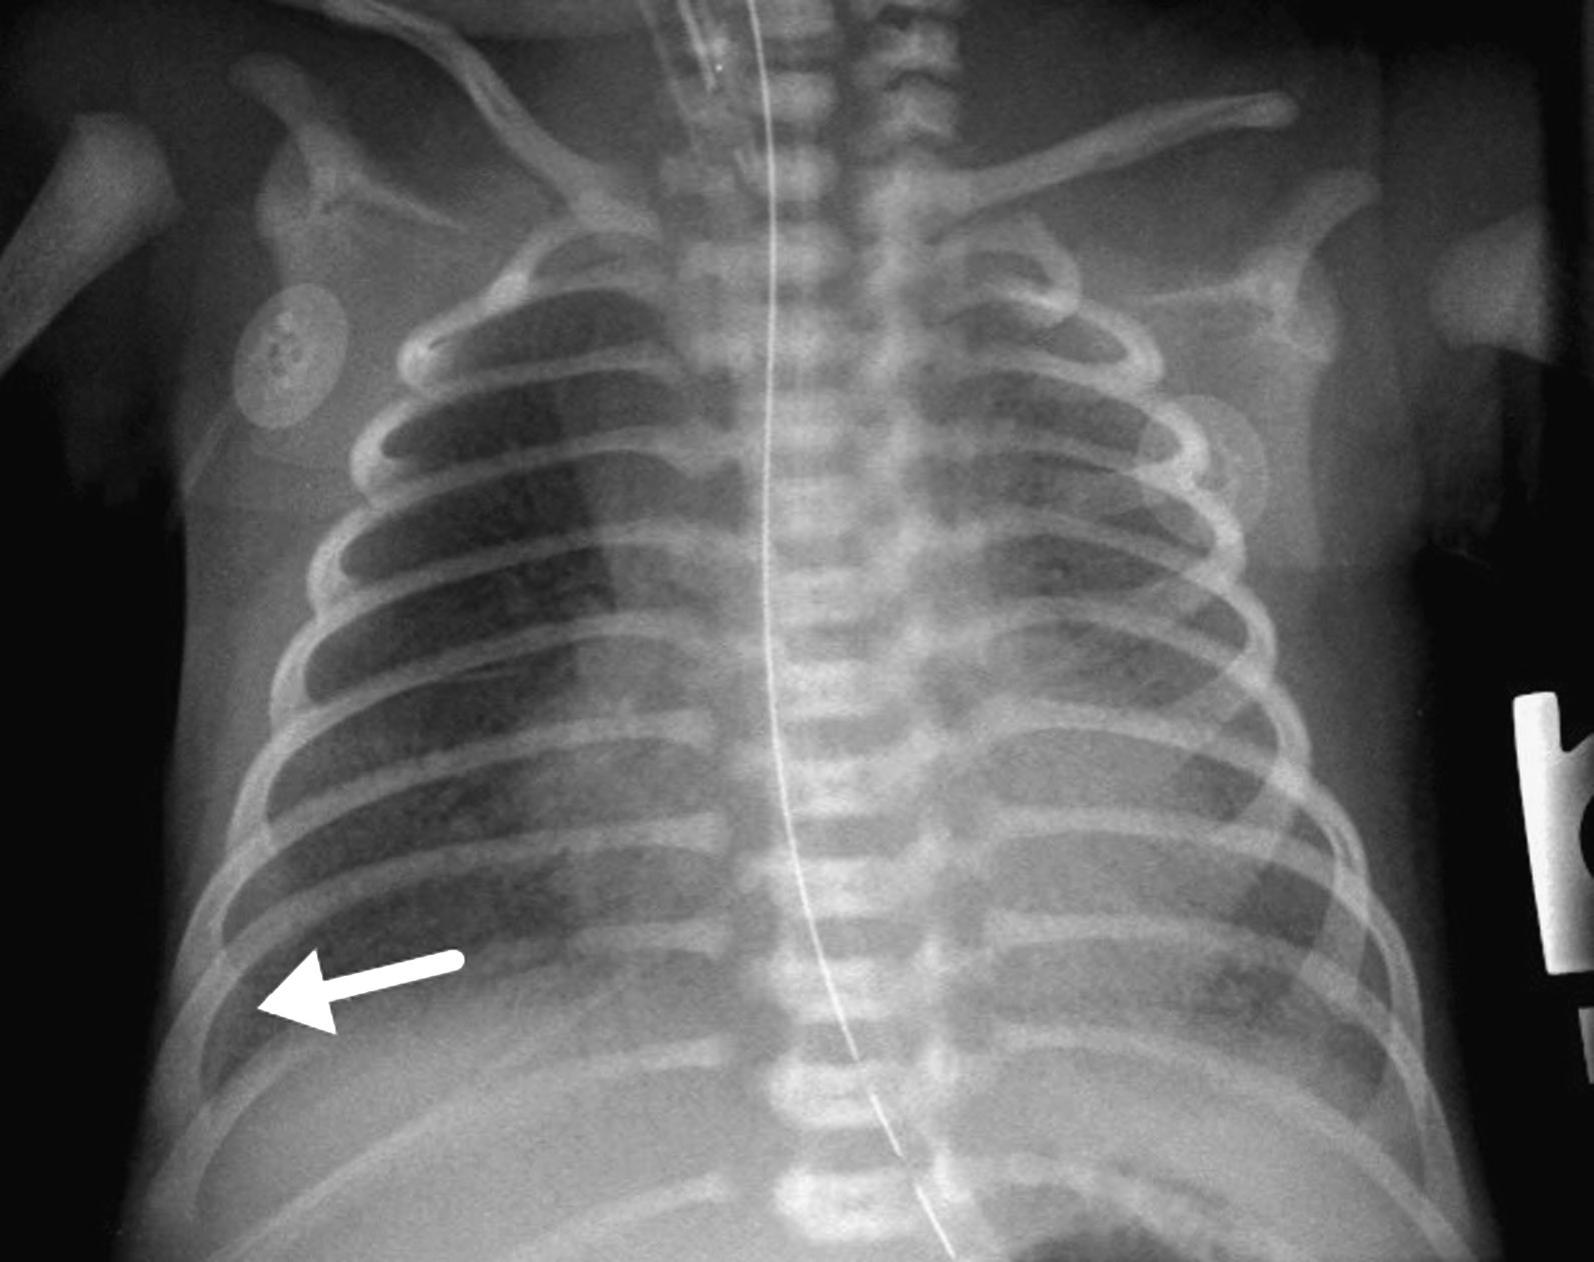

streptococcus is the most common causative organism. Late onset pneumonia usually occurs after discharge; or, in the hospital, it is commonly acquired from the neonatal unit or is associated with mechanical ventilation. Signs of neonatal pneumonia may mimic those of TTN and respiratory distress syndrome (RDS). Nonrespiratory signs include temperature instability, apnea, poor feeding, and lethargy. CXR can have protean imaging manifestations with radiographic findings potentially mimicking those seen in RDS, transient tachypnea of the newborn, and meconium aspiration. Isolated focal consolidation is rare with bilateral airspace disease most common, as seen in Figure 2.1. The presence of a pleural effusion can be a helpful distinguishing feature, being described in up to two-thirds of cases, such as in Figure 2.4.

FIGURE 2.4. Neonatal pneumonia in a neonate with a small right pleural effusion (arrow) and diffuse left and right lower lobe hazy pulmonary opacification.